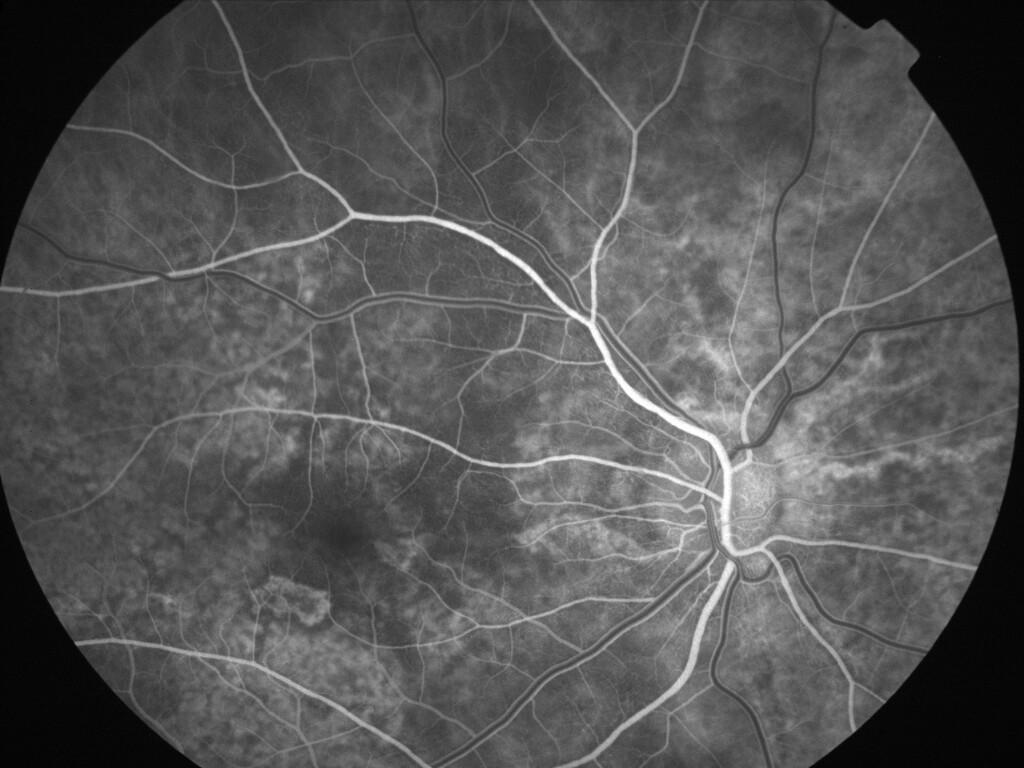

ASSOCIATION STRIES ANGIOIDES ET DYSROPHIE MACULAIRE RETICULEE

NEOVASCULARISATION